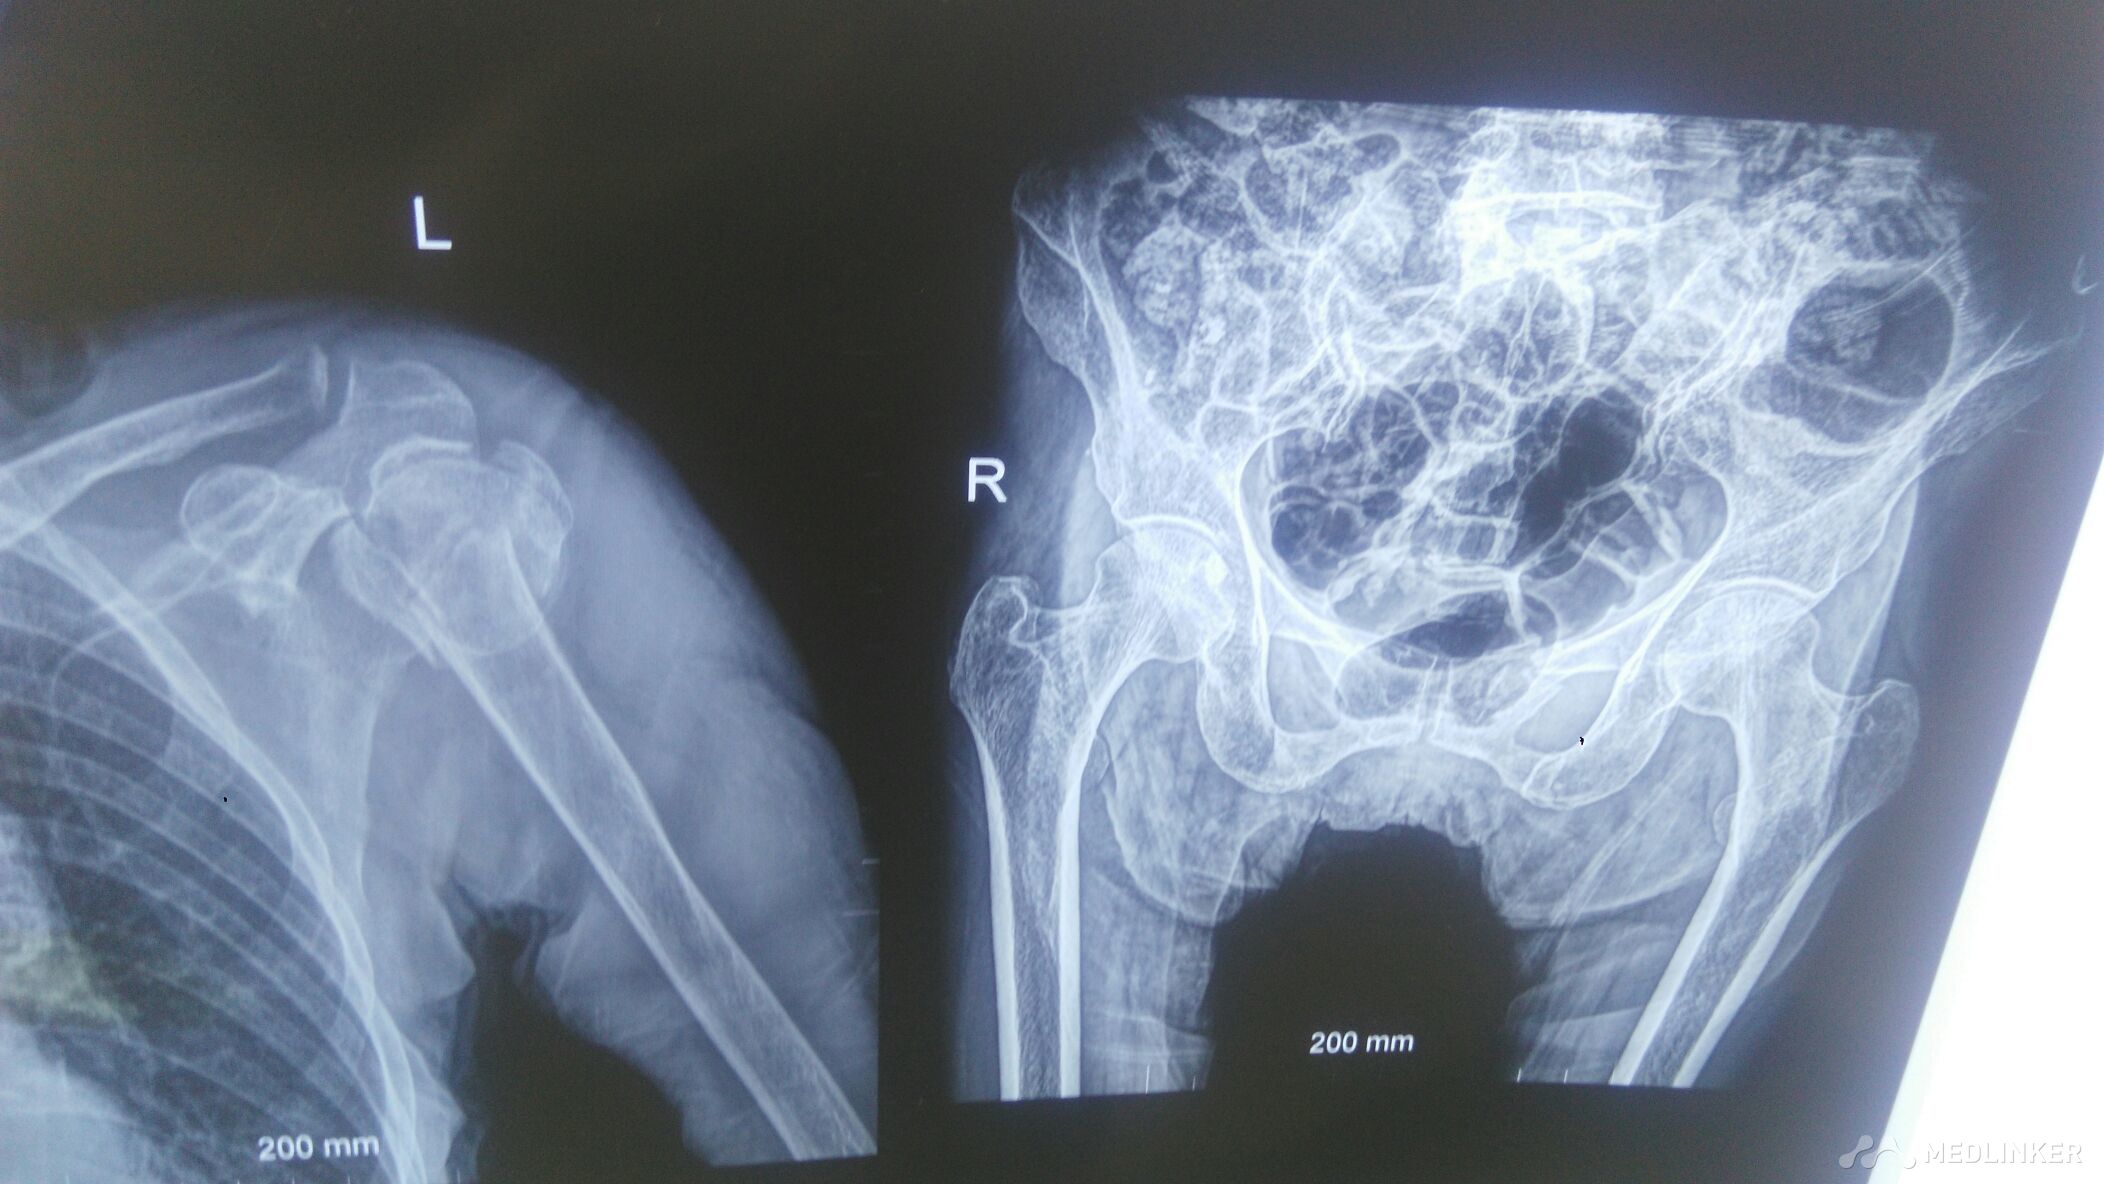

左肱骨近端粉碎性骨折。

左肩部,左髋部肿痛。有高血压,冠心病。左肩部以外科颈处压痛,叩痛阳性。

高龄老人,洗澡时滑倒致左肩部,左髋部肿痛。左肩部,左髋部活动受限。

左肱骨近端粉碎性骨折,左侧耻骨上下支骨折。手术治疗。

86岁的老人,左肱骨近端粉碎性骨折,如果手术治疗。肩部置换最为好。肩部置换术,稳定性难掌握。